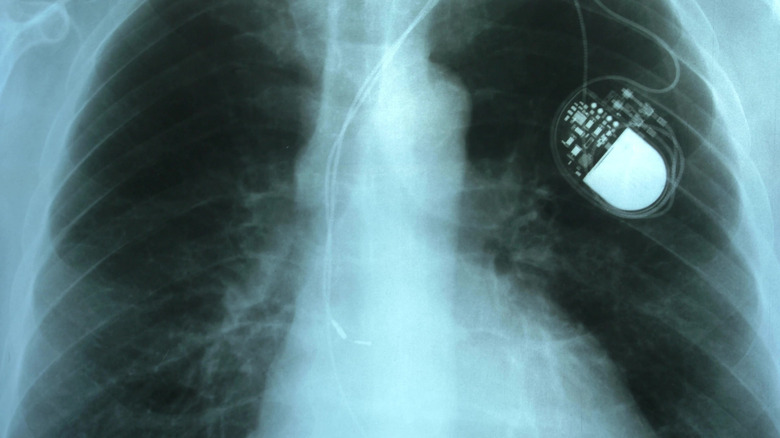

Wilson Greatbatch was an American electrical engineer working in medical research in 1956, when he made a mistake that would change his career — and medicine — forever. He was attempting to build a device that could record heartbeats, but he used the wrong resistor, installing a 1 megaohm component instead of a 10 kiloohm one. Instead of recording the sound of a heartbeat, it produced pulses of its own instead, in a steady, rhythmic beat. Greatbatch instantly realized what this could mean, and he set about creating the first truly portable pacemaker.

Most existing pacemakers leading up to this time were portable only in the sense that they could be unplugged to be moved to another room, then plugged back into the mains. The concept of a pacemaker that would allow the patient to move around freely was revolutionary.

After a few years of development, Greatbatch's invention was installed in its first human patient in 1960, curing his heart block in a way that had never before been possible. Later, Greatbatch also invented the long-life lithium battery that would power the pacemakers for longer. His accidental discovery and subsequent invention was honored in the 1980s when the wearable pacemaker was named one of the top 10 most impressive and influential feats of engineering. Around 200,000 pacemakers are fitted in the U.S. every year, making Greatbatch's invention a crucial part of our modern healthcare system.